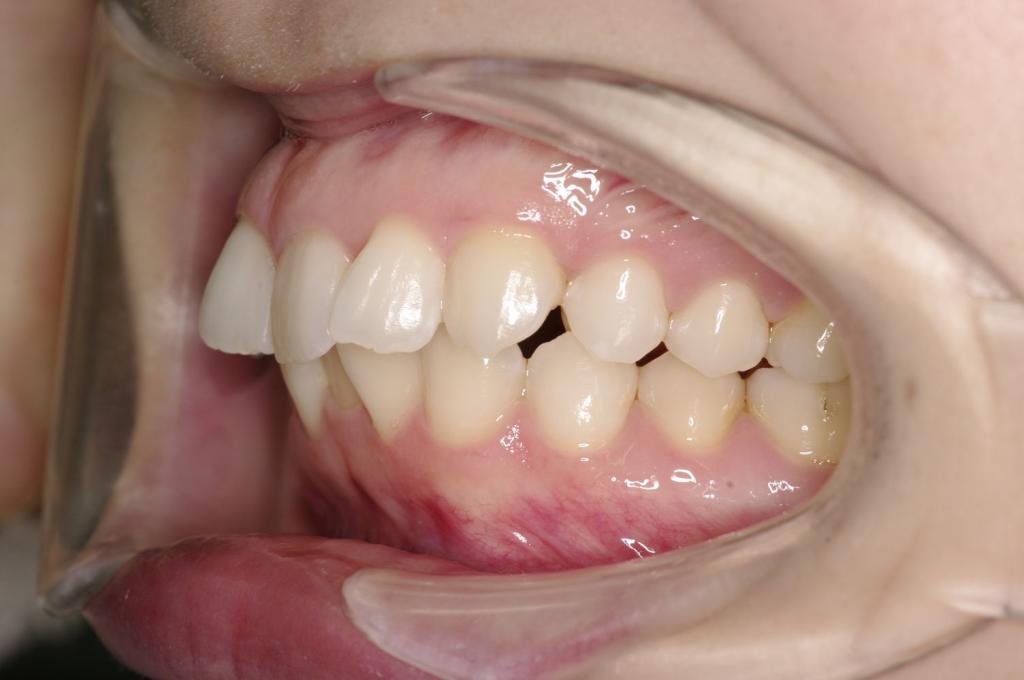

前歯、出っ歯・開咬の矯正治療

(治療期間、治療前後写真、治療方法、費用)WORKS